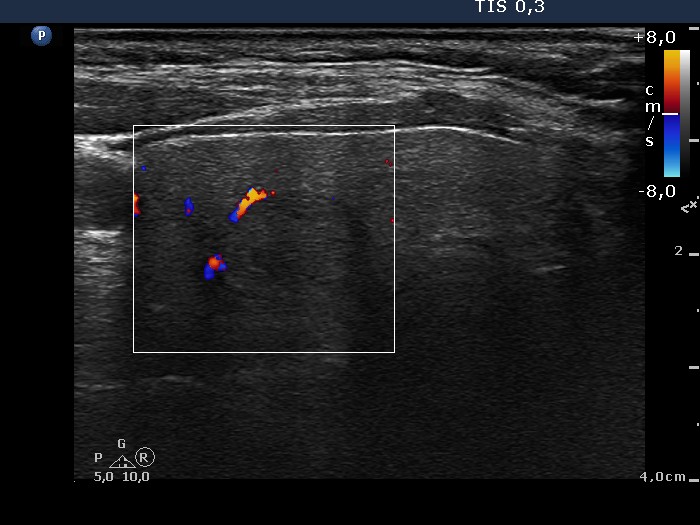

Benign nodular hyperplasia - Case 59. (ultrasonographic picture 6)

Middle-lower part of the right lobe, horizontal view, color Doppler mode. This lesion also displays signs of perinodular blood flow.